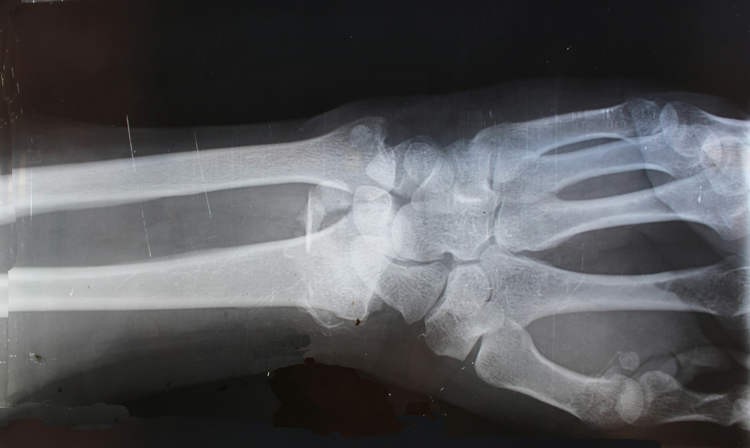

Các nhà phát minh ra Bone-02 đã trình bày một trường hợp thử nghiệm về một bệnh nhân bị gãy cổ tay, được tiêm thuốc qua một vết rạch chỉ dài 3 cm và đã lành lại chỉ trong ba phút. Phẫu thuật để sửa chữa cổ tay sẽ cần một tấm kim loại và ốc vít, việc tháo bỏ chúng sẽ cần một cuộc phẫu thuật thứ hai vào năm sau. Sau ba tháng tái khám, vết gãy của bệnh nhân đã lành hoàn toàn mà không có biến chứng. Đây chỉ là một trong ít nhất 150 trường hợp được ghi nhận sử dụng Bone-02 thành công để điều trị gãy xương.